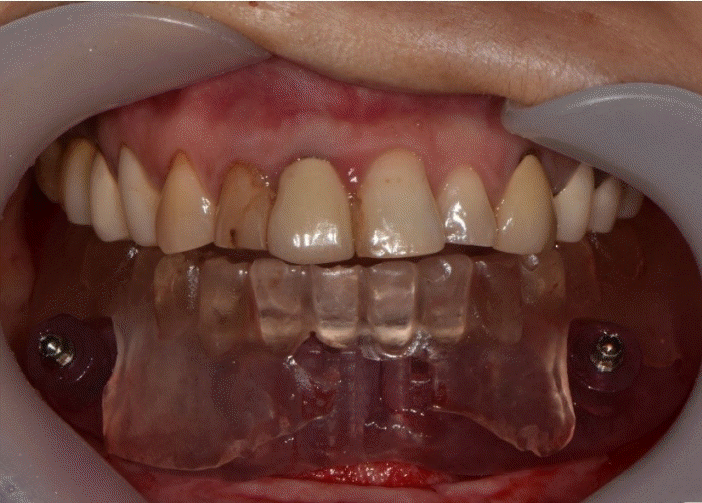

Fig. 12.

Intraoral scan with and without provisional restoration is taken. The occlusion and vertical dimension information is recorded for the final prosthesis.

Fig. 14.

The final prosthesis is functionally and esthetically fitted with the patient. A. Right side view. B. Frontal view. C. Left side view.